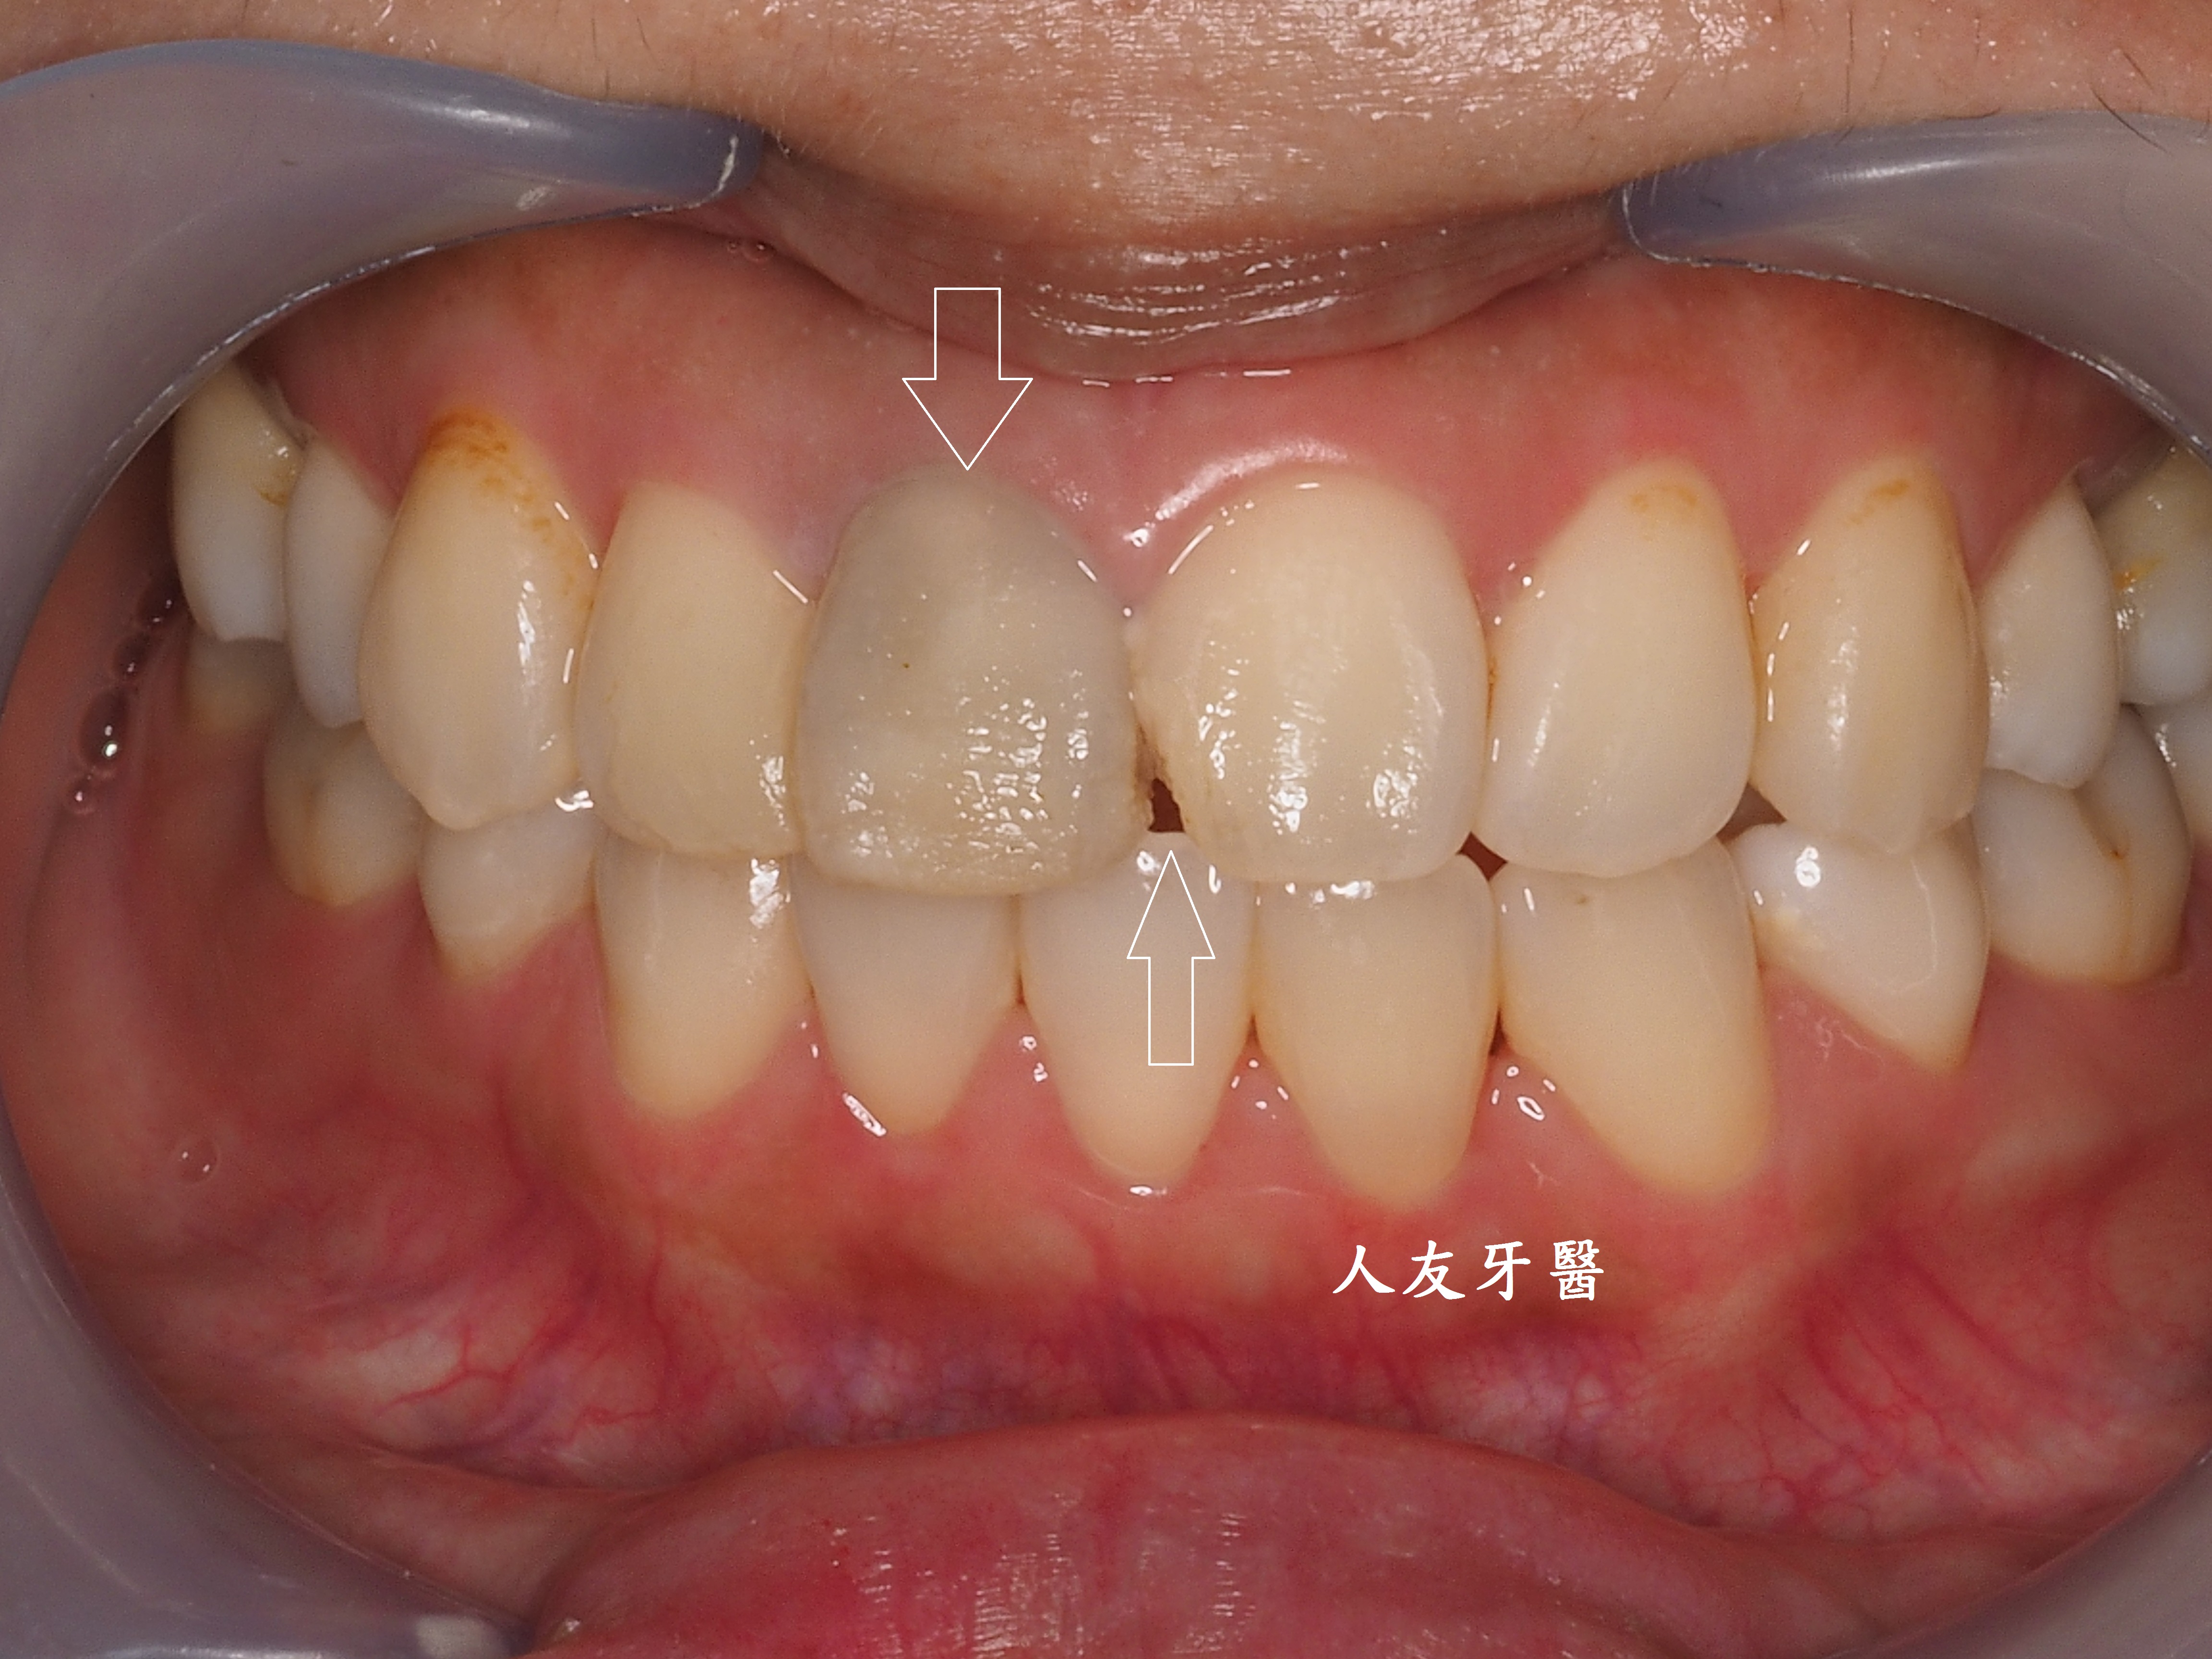

下圖是別家做的牙橋

這位年輕女性患者的門牙和側門牙在別家治療半年,也有做四顆相連的牙橋,一直覺得很不舒服,笑起來不自然也不美觀,聽到鑽牙齒的聲音也很害怕。

想詢問周醫師如何處理。醫師看了X-RAY發現右邊側門牙紅色圓圈的地方有病變,有可能留不住。左邊側門牙藍色箭頭牙齒有裂到肉,也可能留不住。經過討論後建議都拔除。